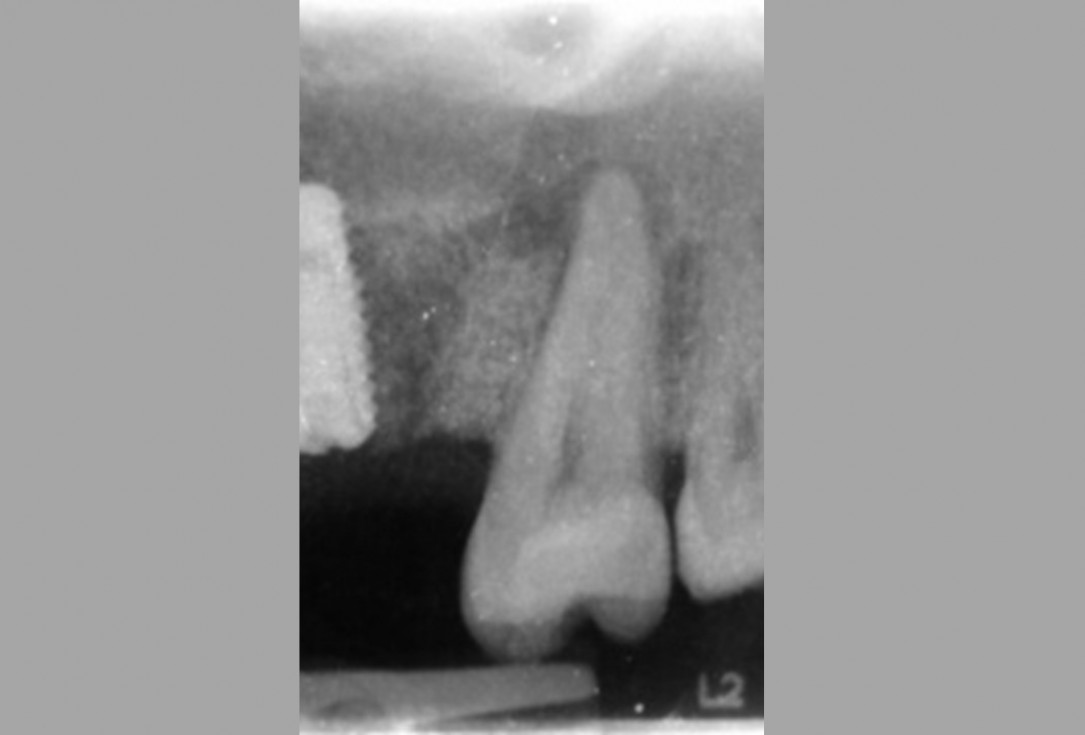

Treatment of vertical bone loss by using cerabone®, autologous bone and Jason® membrane - Prof. Rafael Ortega Lopes

The patient presented with severe pain in the lateral incisor and a deficient adhesive provisional. Bruxism resulted in canine loss and premature contact in the lateral incisor.